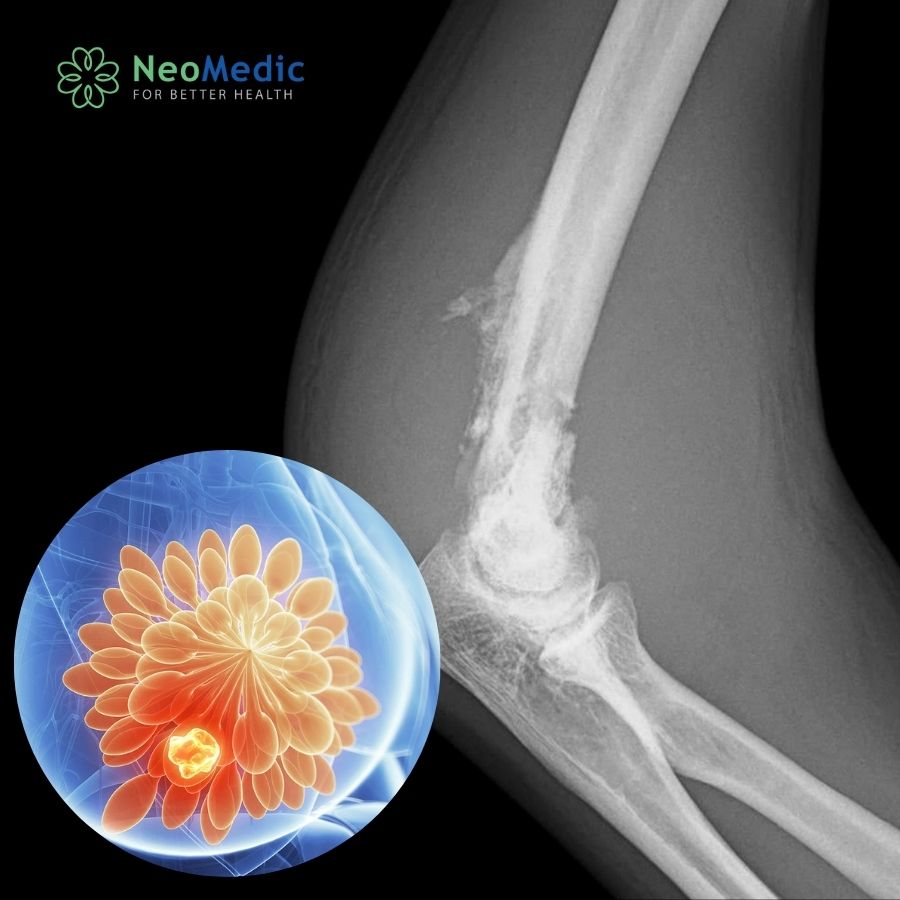

Ung thư vú có di truyền không? Tìm hiểu nguy cơ, yếu tố di truyền và cách phòng ngừa ung thư vú hiệu quả từ chuyên gia.